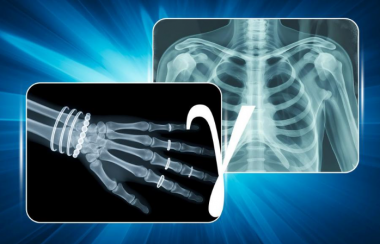

X射线

俄罗斯研发国产X射线轮廓仪 将替代冶金行业进口设备

美国橡树岭国家实验室将核分析代码SAMMY与多功能中子成像仪VENUS结合 实现核材料无损识别新方法